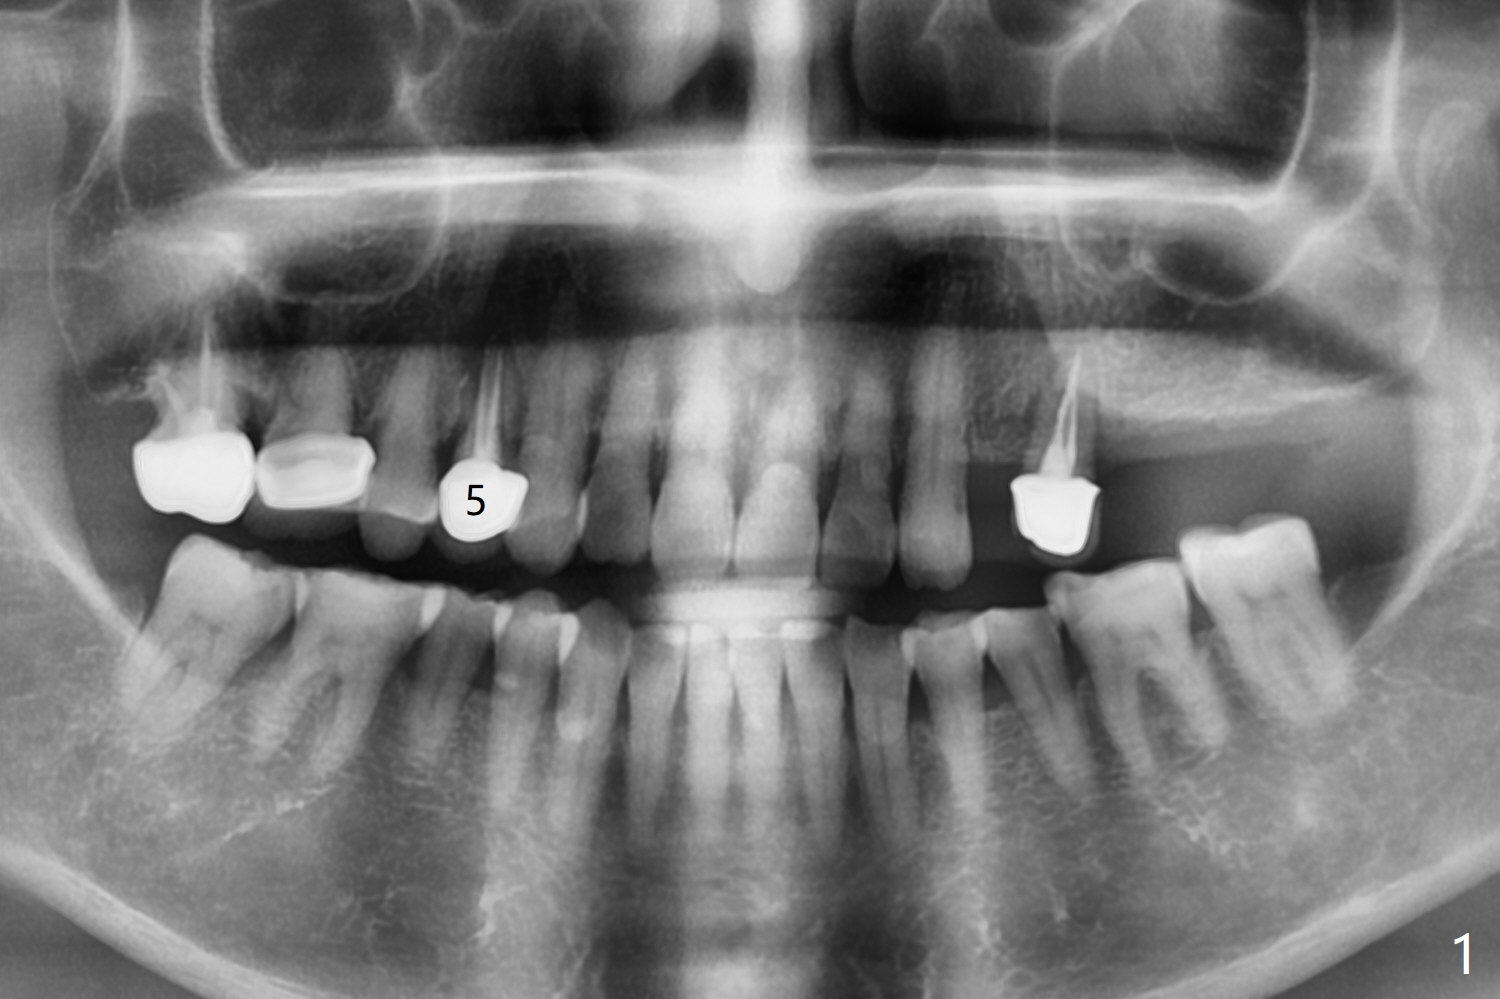

A 74-year-old woman is concerned about buccal fistula of the tooth #5 (Fig.1,2 >). It seems to be safe to place an immediate implant without too much possibility of developing periimplantitis in the future (Fig.3). With guide, restoration could be finished with a 15 degree angled abutment. Remove granulation tissue from the buccal fistula and from the socket. Place a piece of PRF membrane externally (tunnel incision, Fig.4-6 red line) or internally (from the socket) before bone graft (before and after implant placement (Fig.5,6 yellow circles)). Take 5x5 cm CT immediately postop to confirm the repair.